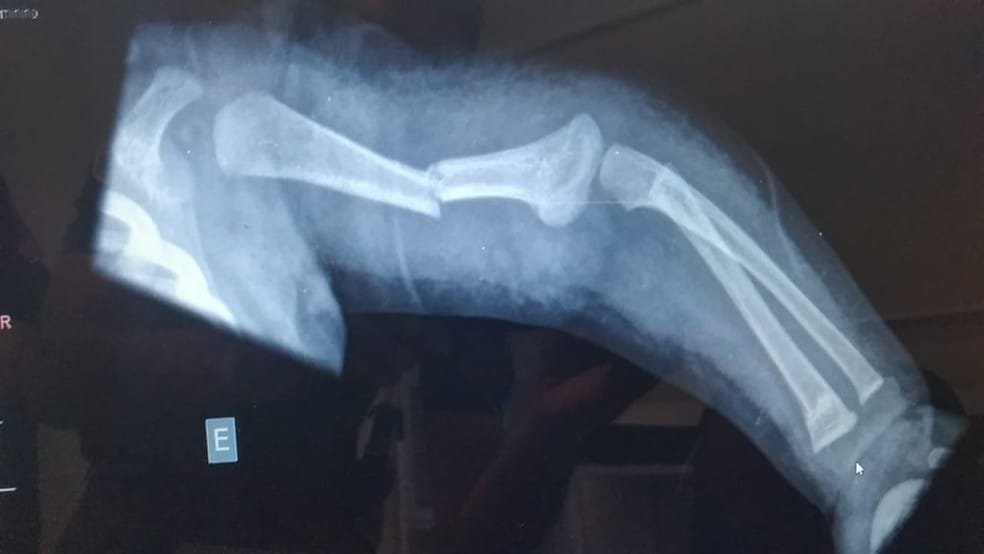

Segundo a PM, a equipe foi acionada por volta das 14h15 pela unidade onde a criança deu entrada com os pais, com fratura em duas partes de um dos braços.